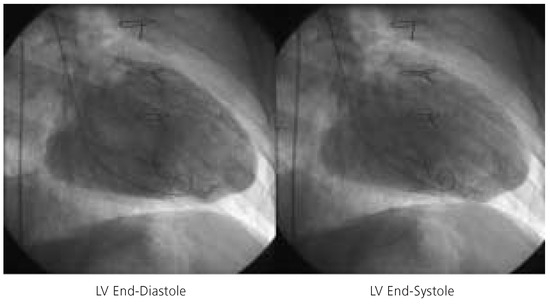

Impella Assisted High Risk Percutaneous Coronary Intervention

by Stephan Windecker and Bernhard Meier

Cardiovasc. Med. 2005, 8(5), 187; https://doi.org/10.4414/cvm.2005.01098 - 27 May 2005

Cited by 1 | Viewed by 105

Percutaneous left ventricular assist devices provide temporary circulatory support as bridge to recovery or heart transplantation in case of severe left ventricular failure and during percutaneous high-risk revascularisation procedures. We describe the first Swiss case of a high risk percutaneous coronary intervention assisted [...] Read more.

Percutaneous left ventricular assist devices provide temporary circulatory support as bridge to recovery or heart transplantation in case of severe left ventricular failure and during percutaneous high-risk revascularisation procedures. We describe the first Swiss case of a high risk percutaneous coronary intervention assisted by a new, percutaneously inserted left ventricular assist device: the Impella Recover® LP 2.5 pump. Full article

Show Figures

Figure 1